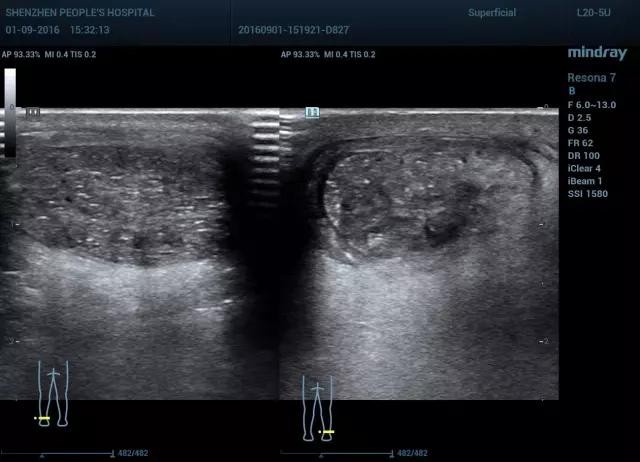

分腱周炎和跟腱炎,急性期跟腱肿胀,活动受限,慢性期疼痛减缓,有疼痛,运动后减缓。腱周炎超声表现为跟腱周围肿胀增厚,回声减低,可出现积液,但跟腱实质回声正常。而跟腱炎常表现为跟腱肿胀增厚,回声减低,实质不均匀,可累及部分或全部腱体,多继发跟骨后滑囊炎。

图11 腱周炎长轴血流双侧对比(图左 正常,图右 血流丰富)

图12 腱周炎短轴血流显示